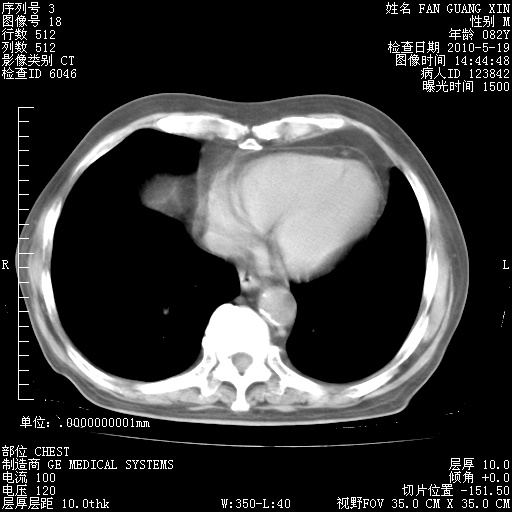

可改为口服强的松40-50mg/d治疗,若病情仍稳定,胸部阴影不再吸收可逐渐减量